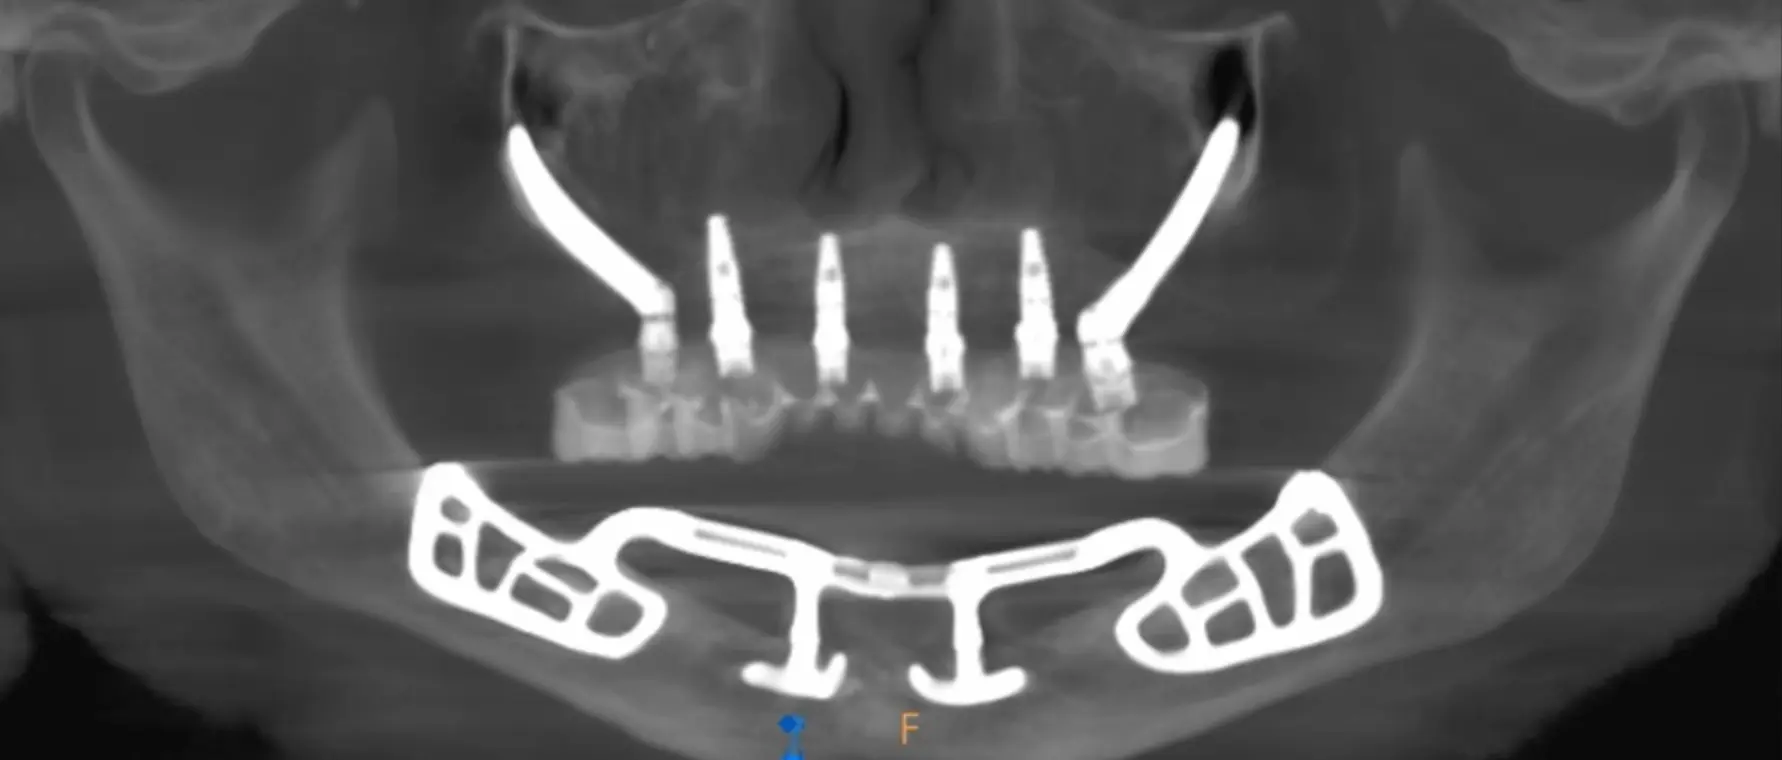

Advanced Full-Arch Reconstruction for the Severely Edentulous

Join Dr. Michael A. Pikos March 20-21, 2026 for his signature Subperiosteal Implant Course inspired by his 35,000 cases of Advanced Full-Arch Treatment, and being the last resort to helping patients when Traditional Implants Are No Longer Viable.